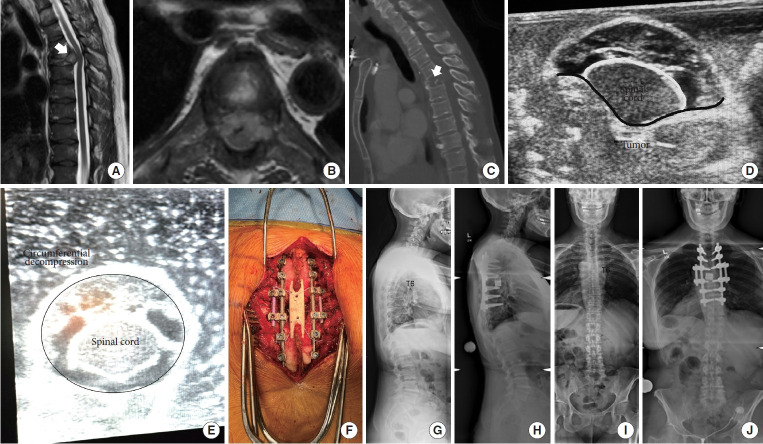

转移性脊柱疾病是一种日益增长的治疗挑战,需要在纳入新兴技术和尊重临床决策基本原则之间取得平衡。辅助治疗的进步,包括立体定向体放疗(SBRT)和化疗,显著提高了患者的长期生存率。手术决策应以完善的框架为指导,如NOMS(神经学、肿瘤学、机械、系统)标准、ESCC(硬膜外脊髓压迫)评分和SINS(脊柱不稳定肿瘤评分),以确保结构化和循证治疗方法。微创技术的整合,包括经皮内固定、消融技术和双门静脉内窥镜入路,降低了手术发病率,促进了更快的恢复。此外,碳纤维植入物通过更好地观察术后任何局部复发和更容易的放射计划,彻底改变了脊柱稳定。SBRT已成为一种关键的方式,提供精确的高剂量辐射,对脊髓的毒性最小,改善局部肿瘤控制和患者预后。多学科方法仍然是最重要的,需要脊柱外科医生、放射肿瘤学家和内科肿瘤学家之间的合作。在这篇叙述性综述中,我们旨在全面概述脊柱转移性肿瘤治疗的现状,重点是:(1)转移性脊柱护理的基础,(2)微创手术技术,(3)碳纤维螺钉的使用,(4)SBRT,(5)最大化患者安全的方法。

Metastatic spine disease represents a growing therapeutic challenge that demands a balance between incorporating emerging technologies while respecting the fundamental principles during clinical decision-making. Advances in adjuvant therapies, including stereotactic body radiotherapy (SBRT) and chemotherapy, have significantly improved long-term patient survival. Surgical decision-making should be guided by well-established frameworks such as the NOMS (neurologic, oncologic, mechanical, systemic) criteria, the ESCC (epidural spinal cord compression) scale, and the SINS (spinal instability neoplastic score), ensuring a structured and evidence-based approach to treatment. The integration of minimally invasive techniques, including percutaneous instrumentation, ablation techniques, and biportal endoscopic approaches, has reduced surgical morbidity and facilitated faster recovery. Additionally, carbon fiber implants are revolutionizing spinal stabilization by allowing better postoperative visualization of any local recurrence and easier radiation planning. SBRT has emerged as a critical modality, offering precise, high-dose radiation with minimal toxicity to the spinal cord, improving local tumor control and patient outcomes. A multidisciplinary approach remains paramount, requiring collaboration between spine surgeons, radiation oncologists, and medical oncologists. In this narrative review, we aim to provide a comprehensive overview of the current state of metastatic spine tumor management, focusing on: (1) fundamentals of metastatic spine care, (2) minimally invasive surgical techniques, (3) the use of carbon fiber screws, (4) SBRT, and (5) ways to maximize patient safety.